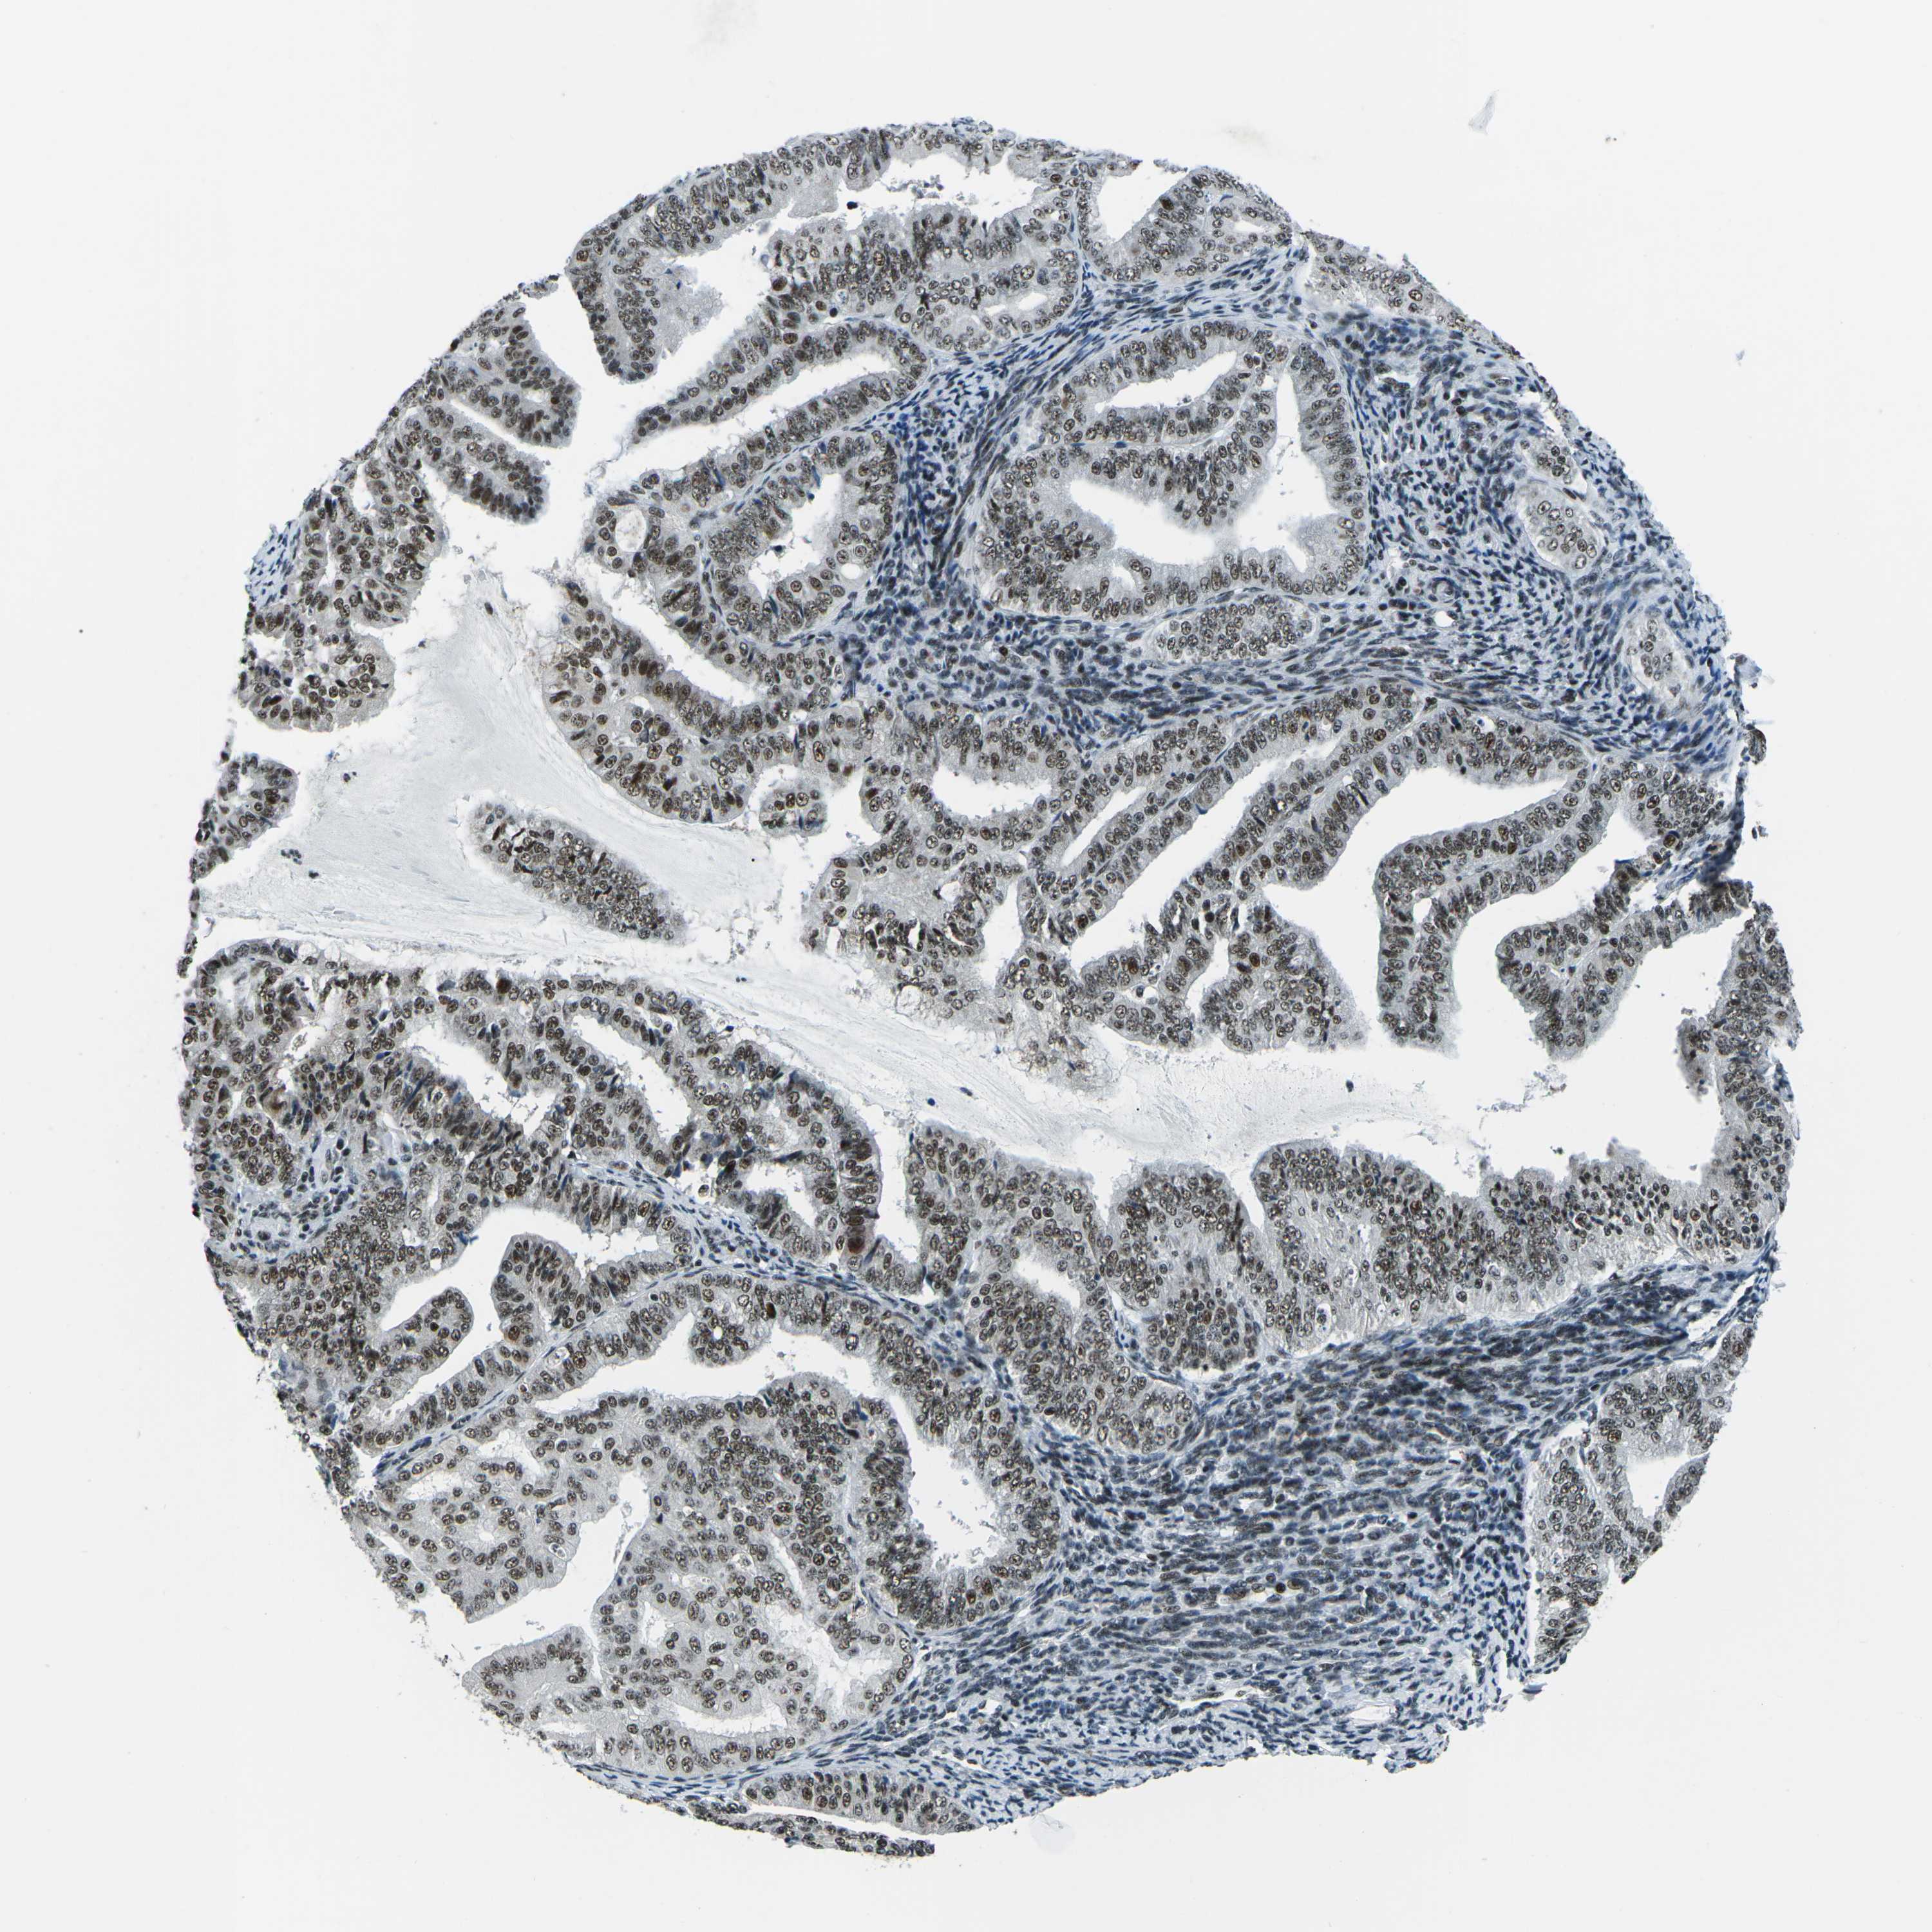

ENDOMETRIAL CANCER - Protein expressioni

A mouse-over function shows sample information and annotation data. Click on an image to view it in a full screen mode. Samples can be filtered based on level of antibody staining by selecting one or several of the following categories: high, medium, low and not detected. The assay and annotation is described here.

Note that samples used for immunohistochemistry by the Human Protein Atlas do not correspond to samples in the TCGA dataset.

Antibody stainingi

Antibody staining in the annotated cell types in the current human tissue is reported as not detected, low, medium, or high, based on conventional immunohistochemistry profiling in selected tissues. This score is based on the combination of the staining intensity and fraction of stained cells.

Each image is clickable and will lead to virtual microscopy that enables deeper exploration of all samples and also displays staining intensity scores, fraction scores and subcellular localization as well as patient and tissue information for each sample.

Antibody HPA019703

Antibody CAB016547

Staining

High

Medium

Low

Not detected

Intensity

Strong

Moderate

Weak

Negative

Quantity

>75%

75%-25%

<25%

None

Location

Nuclear

Cytoplasmic/membranous

Cytoplasmic/membranous,nuclear

Adenocarcinoma, NOS

Adenoma, NOS